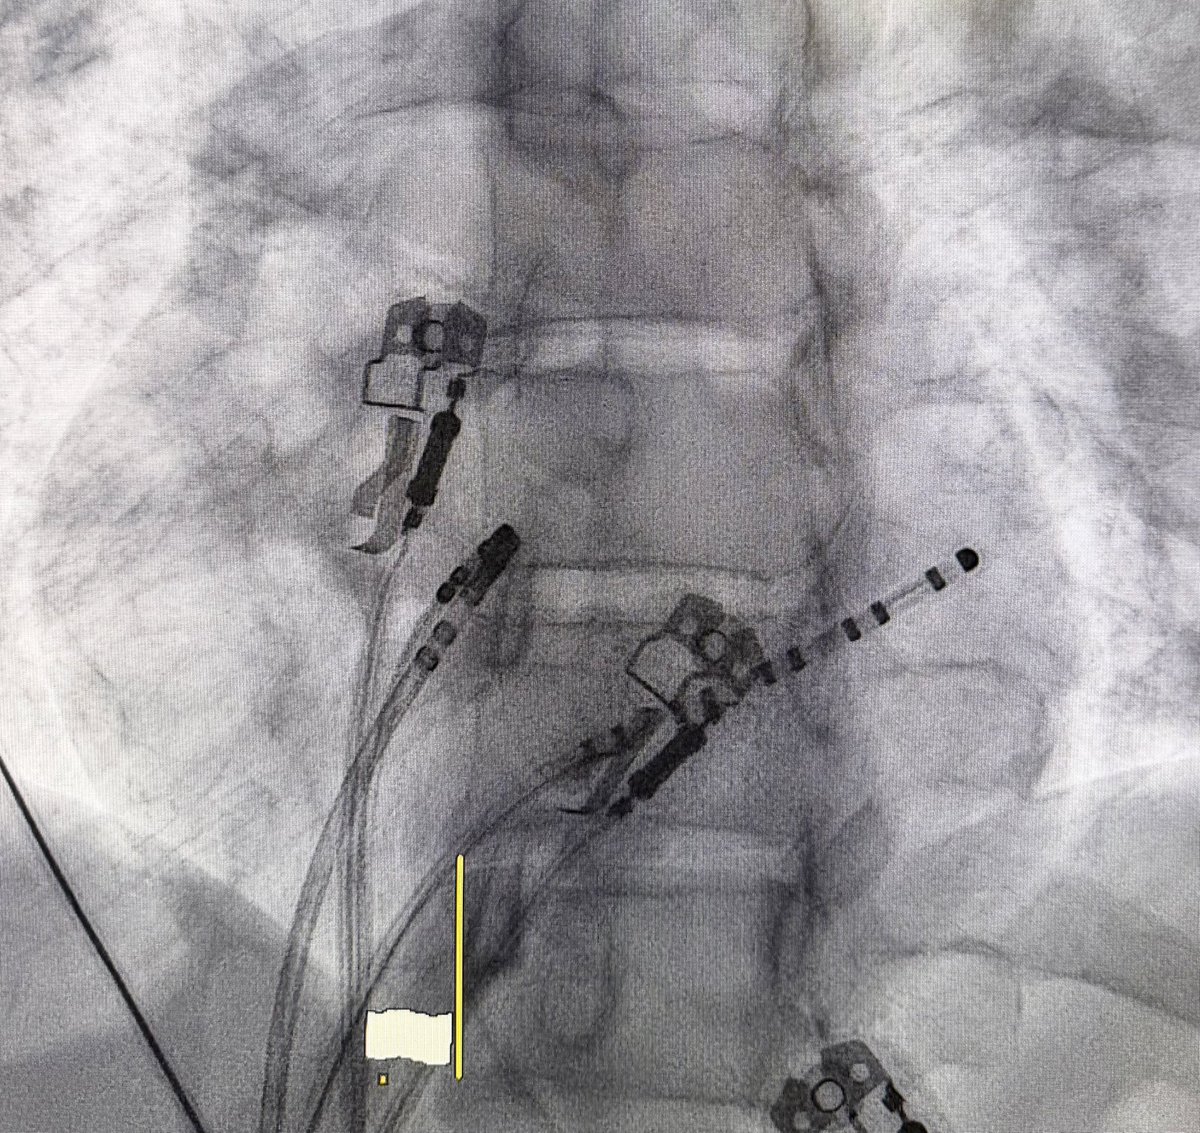

@Ecgloverr @ALFIEEP1 @ProfDConnelly @adribaran @SergioPinski @EPWaveDoc @KostekMilan @ArshadEP277 @UlhasDr @DrRoderickTung @DaveRichley @javadm20 Wide QRS tachycardia with LBBB morphology, in a young patient with axis and morphology similar to sinus rhythm. Altered basal ECG: QS V1-5. I'm inclined to think about supraventricular tachycardia with aberrance.

@IsaParam Two pathways(Lateral and Septal) initiated by Extra stim pacing on CS 9-10. Hard to rule out AT without calipers but VA does not seem to wobble too much(less likely). Lastly, AH jump seems to initiate the tachycardia further indicating that the AV node is part of the circuit.